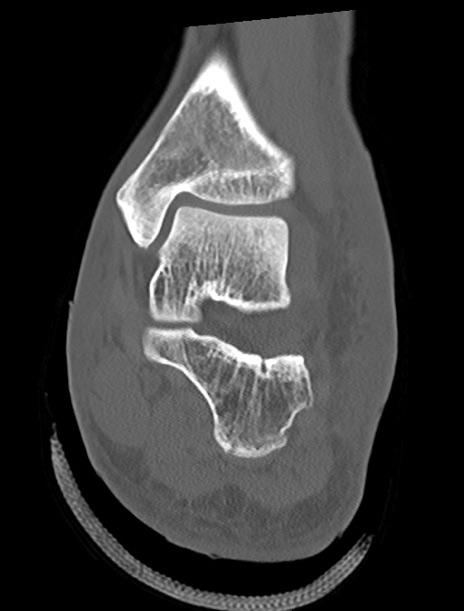

左足関節CT

矢状断像